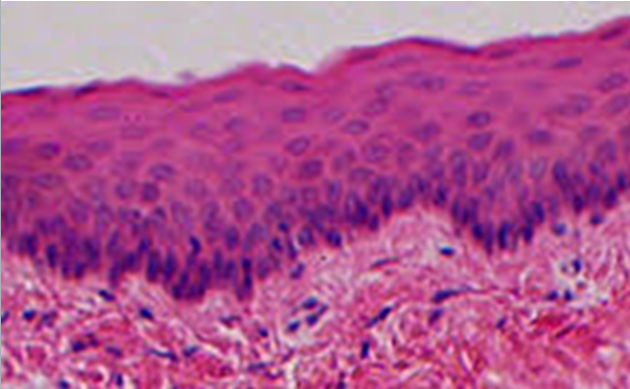

LM picture of non-keratinized strartified squamous epithelium